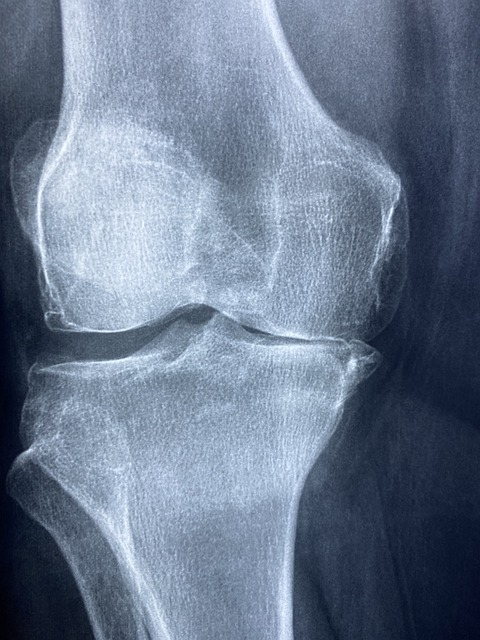

이미 진행된 퇴행성 관절염을 조금이라도 더 느리게 오게 막으려면 나의 무릎관절염 진행 상태를 아는 것이 중요합니다. 퇴행성 관절염은 관리를 하지 않으면 더 빨리 닳는 특징이 있으며, 부분적으로 닳은 관절을 재생하는 방법은 있으나 완전히 닳아버린 연골을 다시 회복하기는 어렵기 때문입니다. 관절염이 심하게 진행되지 않고 부분적으로 닳았으면 몸에 해롭지 않고 내성도 없으며 무릎관절염의 진행을 막을 수 있는 좋은 주사들이 나와있습니다. 연골주사나 프롤로주사, DNA주사등이 있고 이 중에서 건강보험이 되는 주사가 있으니 잘 알고 선택하여 맞으시는 방법도 있습니다.